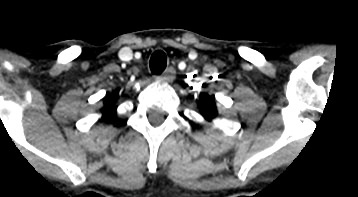

Мультиспиральная компьютерная томография – это высокоинформативный лучевой метод диагностики различной патологии мягких тканей шеи, включая воспалительные заболевания, травматические повреждения и опухолевые процессы. КТ позволяет оценить состояние щитовидной железы, паращитовидных желез, гортани, верхней части пищевода, магистральных сосудов шеи, шейных лимфоузлов и окружающих мягких тканей.

Для контрастирования используется йодсодержащее контрастное вещество, которое в составе рентгеноконтрастного препарата вводится в вену пациенту непосредственно во время исследования. Благодаря способности контраста поглощать рентгеновские лучи на снимках КТ хорошо контрастируются кровеносные сосуды и опухолевые образования, имеющие, как правило, развитую сосудистую сеть. Методика внутривенного болюсного контрастирования помогает обнаружить воспалительные изменения, отличить доброкачественные опухоли от злокачественных, выявить поражение лимфатических узлов и степень прорастания опухоли в магистральные сосуды и окружающие ткани.

Данное обследование позволяет оценить состояние следующих анатомических структур:

• щитовидная железа (размеры органа, однородность структуры, кисты, узловые образования, опухоли);

• паращитовидные железы (количество, размеры, точная локализация желез, нетипичное расположение, формирование кистозных образований, аденом, опухолевых узлов);

• гортань (состояние костного скелета и хрящей гортани, заболевания голосовых связок, опухолевые образования, полипы, аномалии развития);

• трахея (состояние хрящевого скелета трахеи, наличие инородных предметов, доброкачественных и злокачественных образований);

• пищевод (состояние слизистой и стенок пищевода, наличие дивертикулов, инородных тел, опухолевых образований);

• состояние регионарных лимфоузлов;

• состояние магистральных сосудов шеи, кровоснабжающих головной мозг (аномалии развития, сужения, аневризмы артерий);